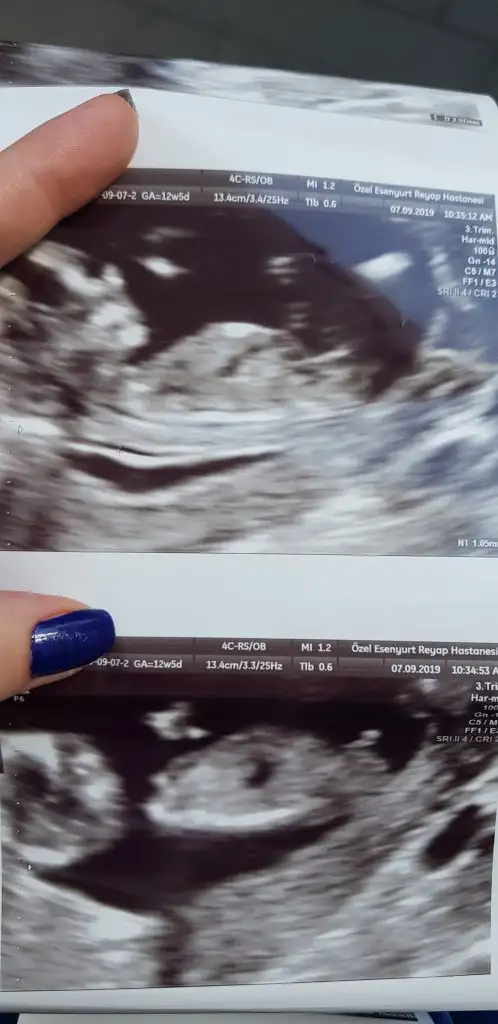

Benim tahmin canım en iyisini rabbim bilir gönlünüzdeki olur inşallah saglıkla usgnizde kız görünüyor inşallah dr da gönlünüzdekini söylerYorumlar için çok teşekkür ederim ☺Maalesef en net verdiği görüntüler buBir tane oğlum var, ailede de hiç kız yok.Gönülden geçen kız olsa da , yine de şaşırırım kız çıkarsa

Allah hepimize sağlıklı, hayırlı evlat versin...Gerisi teferruatYorumlar için çok teşekkür ederimMaalesef en net verdiği görüntüler bu Bir tane oğlum var, ailede de hiç kız yok.Gönülden geçen kız olsa da , yine de şaşırırım kız çıkarsa

Net olmamakla birlikte kız

Doktor yuzde 60 erkek ama degisebilir dedi ins senin dedigin cikar:)Net olmamakla birlikte kız